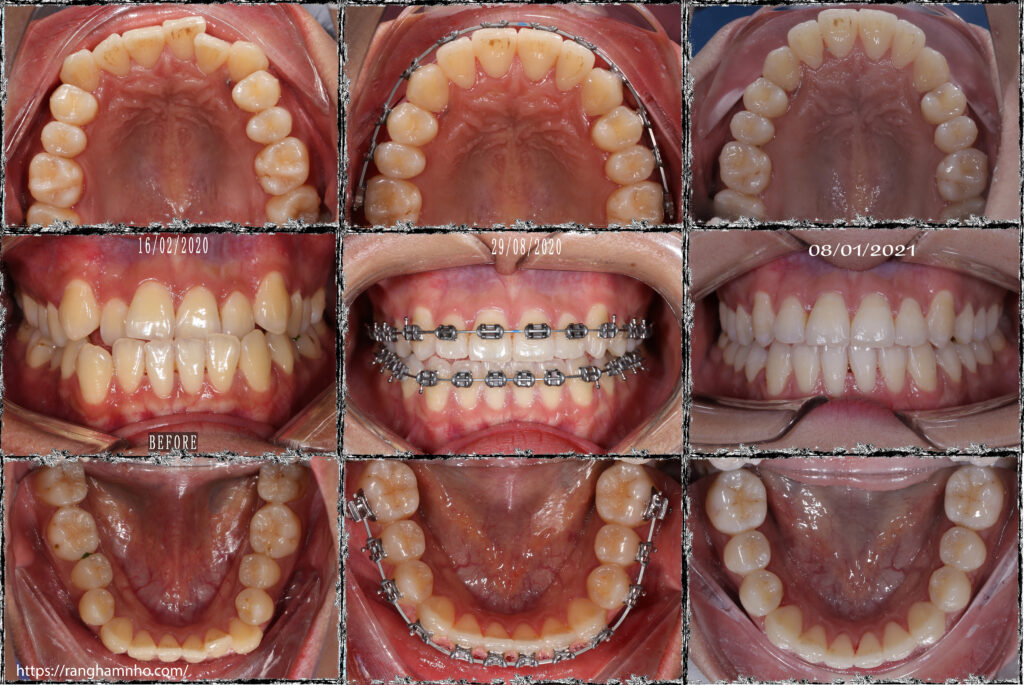

BN nữ sinh năm 1997 đến phòng khám với tình trạng khớp cắn ngược, răng hàm dưới nằm phủ ngoài răng hàm trên. Cung hàm trên hẹp, răng chen chúc. Cả hai cung răng hàm trên và hàm dưới có dạng vuông, khuôn răng rộng cười kém tươi.

Kế hoạch điều trị: Sử dụng toàn bộ là dây cung Damon không thay đổi quá nhiều hình dạng cung răng.

Nụ cười móm của bệnh nhân đã hoàn toàn được thiện, khuôn cười thay đổi tích cực